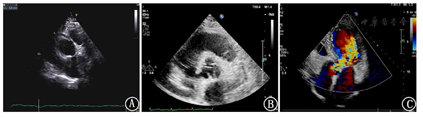

超声心动图所见:左房、左室稍大,升主动脉增宽,窦管连接部基本消失,主动脉根部右冠窦至无冠窦可见一纤细强回声光带,将主动脉根部分为两个腔,左冠状动脉起始部位置正常,内径约0.34cm,右冠状动脉起始部位于大动脉根部短轴约12~1点钟方位,似位于假腔,内径稍宽约0.48cm,升主动脉近端、主动脉根部及降部未见异常光带回声。室间隔与左室壁稍厚,室壁运动可,未见明显节段性室壁运动异常;CDFI示主动脉瓣中-重度反流,呈偏心性,沿二尖瓣前瓣走行。

超声提示:1、主动脉瓣中-重度关闭不全;2、主动脉窦部异常回声光带、右冠状动脉稍增宽(建议CTA除外主动脉窦部夹层累及右冠状动脉及主动脉瓣)(图4)。

经胸超声心动图虽然对心外结构显示价值有限,但能精细显示主动脉根部病变、主动脉瓣是否受累及瓣膜反流程度、冠状动脉是否受累及合并节段性室壁运动异常等心肌缺血表现,还能准确评估心脏的收缩和舒张功能[6]。此病例患者因其主动脉夹层累及部位特殊且局限,胸痛三联CTA漏诊,而经胸超声心动图对主动脉根部病变的显示优势帮助明确诊断并为临床及时正确处理提供依据。